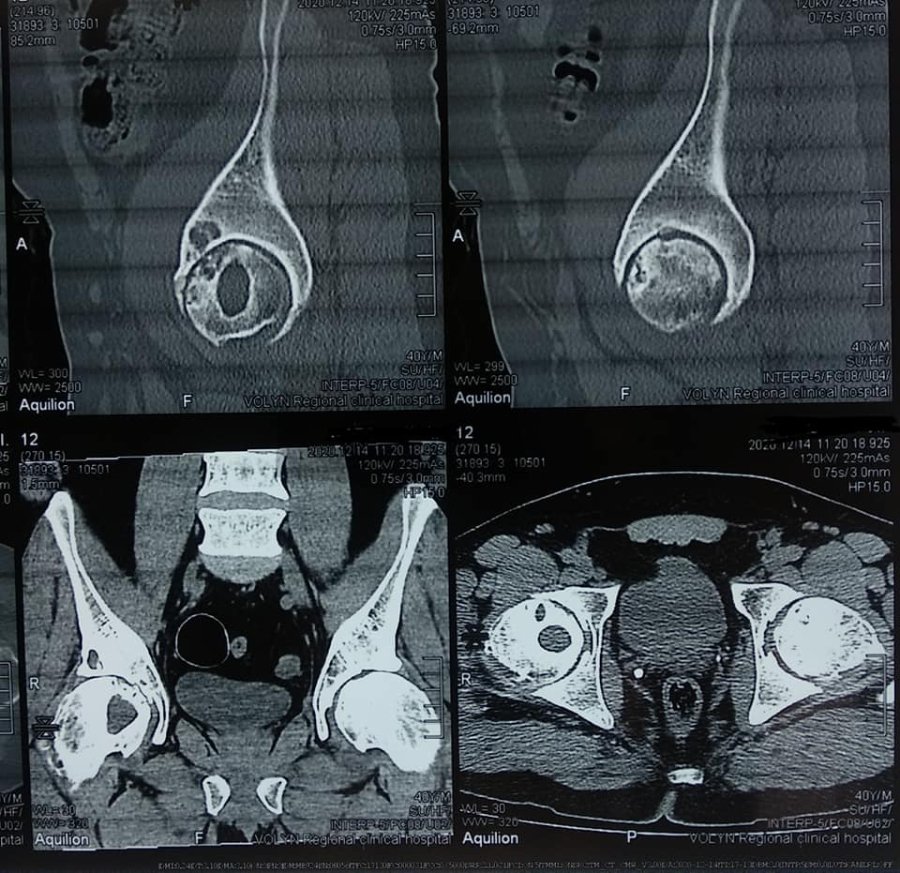

В ході подальшого дослідження в головці правої стегнової кістки виявили кисту розмірами 2*2*2,5 см.

"В ході клінічного розбору було прийняте рішення на користь органозберігаючої операції. Куратор напрямку пухлин та пухлиноподібних захворювань Шевчик Я.В. виконав унікальну операцію: декомпресійну пластику кисти головки стегнової кістки", - йдеться в дописі.